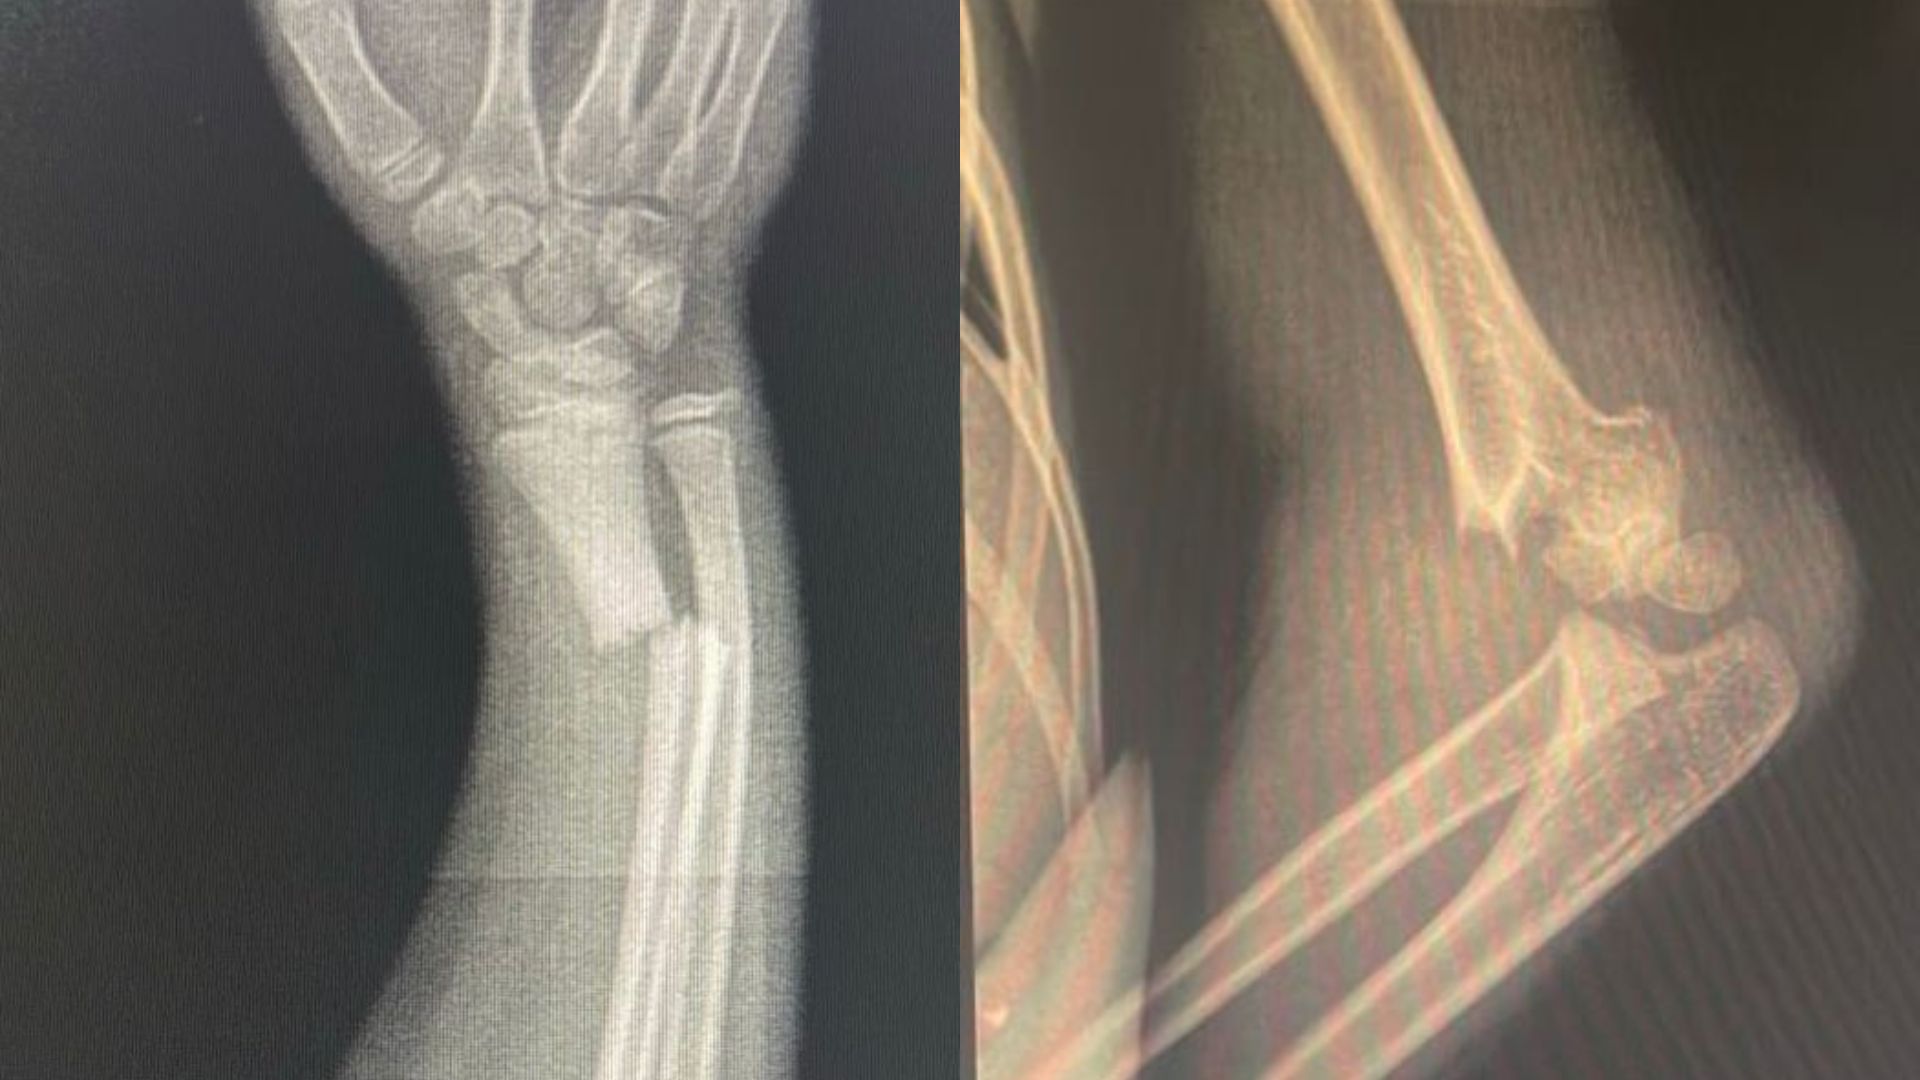

Essa realidade começou a mudar. O Hospital Municipal Alfredo Abrahão tornou-se o novo centro de referência para traumas ortopédicos infantis, com atendimento 24 horas. Só nos últimos dias, várias crianças com fraturas graves foram operadas aqui mesmo — tratadas com sucesso, em hospital público e dentro da própria rede municipal.

Há, naturalmente, situações que ainda exigem transferência — como o caso de fratura de fêmur. Mas isso não representa falha, e sim responsabilidade técnica, já que o hospital ainda não possui habilitação para procedimentos de alta complexidade. A regulação segue protocolos que priorizam o cuidado e a segurança do paciente.